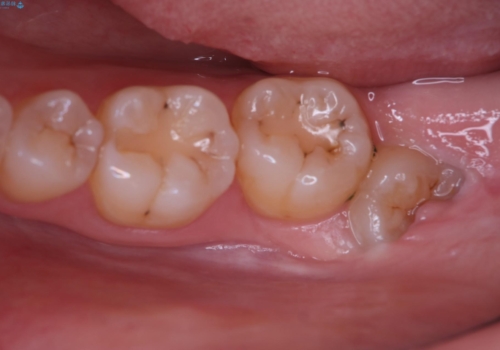

- 下の親知らずは一部分歯肉が被っていたため汚れが溜まりすく、磨き残しにより炎症が生じていました。

抜歯を提案した所希望されたので上下同時に抜歯を行いました。

親知らずは磨きにくく汚れが溜まりやすい場所です。

磨き残しによって親知らずだけでなく、その影響で接してる一つ手前の歯まで虫歯や歯周病のリスクが高くなるため、抜歯をおすすめします。